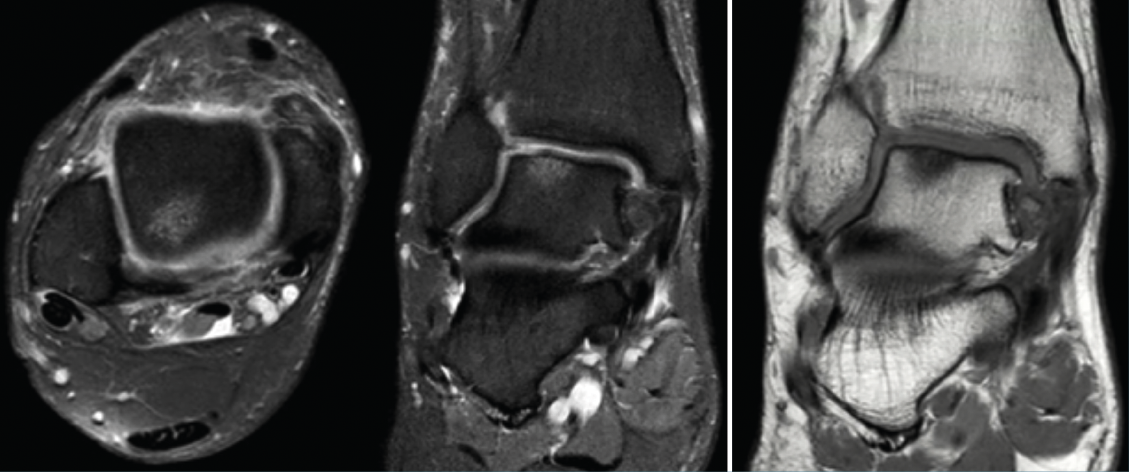

Se solicitó resonancia magnética (RM) y tomografía axial computarizada (TAC) del tobillo afecto a los 6 meses del traumatismo, en las que se observó una lesión osteocondral en la cúpula astragalina de 15 × 11 mm (diámetro anteroposterior y medial-lateral) según la RM y de 9 × 7 mm según la TAC (Figura 2). No se observó lesión capsuloligamentosa. Sí que se detectaron pequeños cuerpos libres en el receso capsular posteroexterno y anteromedial.

Figura 2. Imágenes de resonancia magnética (RM) en T2 (corte sagital y coronal). Imagen de la tomografía axial computarizada (TAC), corte coronal. Se observa una lesión osteocondral en la cúpula astragalina de 15 × 11 mm (diámetro anteroposterior y medial-lateral) según la RM y de 9 × 7 mm según la TAC.